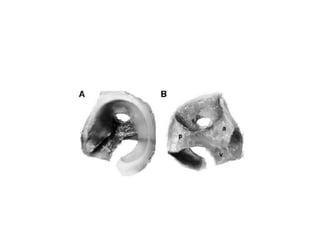

Coxa magna and FAI

• Coxa magna results due to physeal growth

disturbance caused by ischemia

• Causes FAI

• cam (commonly seen in LCPD) and pincer

types

Managemnt of coxa magna

• Treatment revOlutionalized after Reinhold Ganz

who introduced safe surgical dislocation

method

• Femoral head reduction surgery (FHRO)